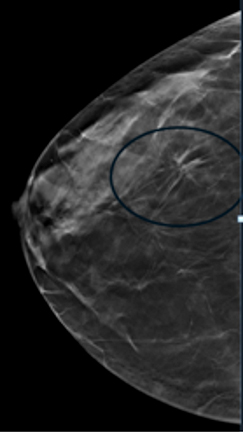

Compare these two images. You can see the benefits of 3D tomosynthesis. A small cancer (circled) on tomosynthesis slices in image A (left) is not apparent in the standard 2D mammogram, image B (right) of the same patient and same projection.